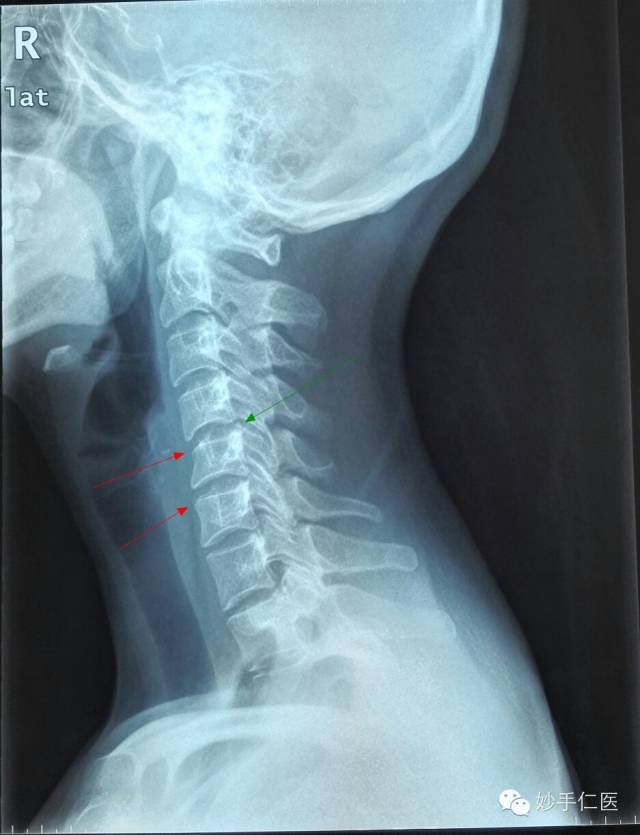

颈部侧位片子:颈部曲度消失,出现颈部反向弯曲(绿色箭头);颈5、颈6椎体前缘出现骨质代偿性改变(红色箭头)。